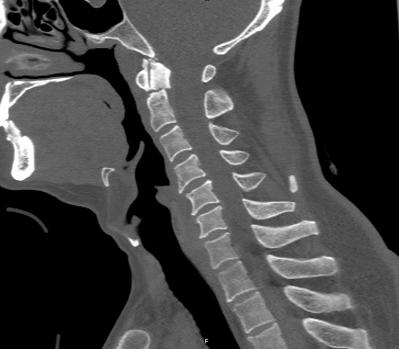

近日,45岁的王先生因高处坠落伤致颈部疼痛、活动受限,于是到北京友谊医院就诊。结合CT结果,医生诊断王先生为枢椎齿状突II型骨折,需手术治疗,王先生被收入骨科病房。

辅助检查显示:颈椎前部可及多发血肿,枢椎齿状突骨折部位向后方移位。

术中,手术团队对王先生颈部重要的组织结构均进行了较好的保护,而且一次性成功的置入空心钉固定骨折断端。手术持续了近5个小时,术后王先生症状明显缓解,无神经损伤。术后复查X线显示齿状突复位,螺钉位置良好。目前王先生已顺利出院,并对北京友谊医院骨科中心的服务进行了高度的评价。

术后显示齿状突复位,螺钉位置良好